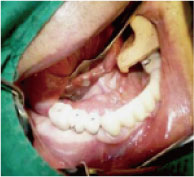

DIO NAVI surgery is planned after 3D computer simulation surgery is done, and it is up-to-date digital navigation implant surgery done with minimal incision and little pain in short time.